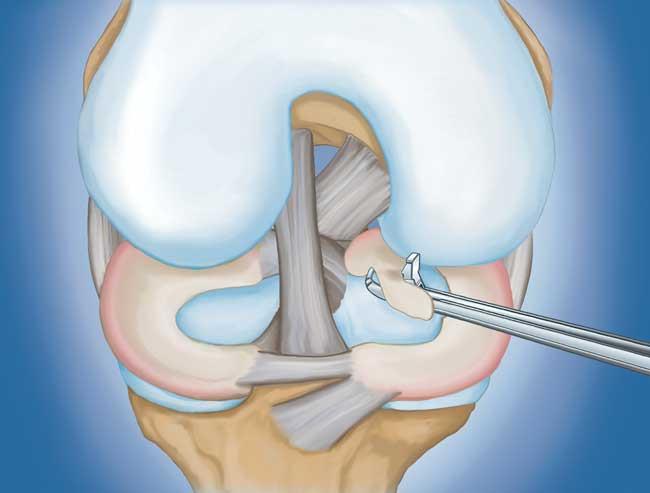

程序。  膝關節鏡檢查是最常進行的外科手術之一。在這個過程中,外科醫生通過膝蓋上的一個小切口(入口)插入一個微型相機。這提供了膝蓋內部的清晰視圖。然后外科醫生通過兩個或三個其他小入口插入手術器械以修剪或修復撕裂。

插圖和照片顯示了通過膝蓋入口插入的照相機和儀器

• 部分半月板切除術。  在這個過程中,受損的半月板組織被修剪掉。該程序通常允許在手術后立即負重和全方位運動。

• 半月板修復。  一些半月板撕裂可以通過將撕裂的碎片縫合(縫合)在一起來修復。撕裂能否成功修復取決于撕裂的類型,以及受傷半月板的整體狀況。因為半月板必須一起愈合,修復的恢復時間比半月板切除術長。

部分半月板切除術特寫

用縫線修復撕裂的半月板